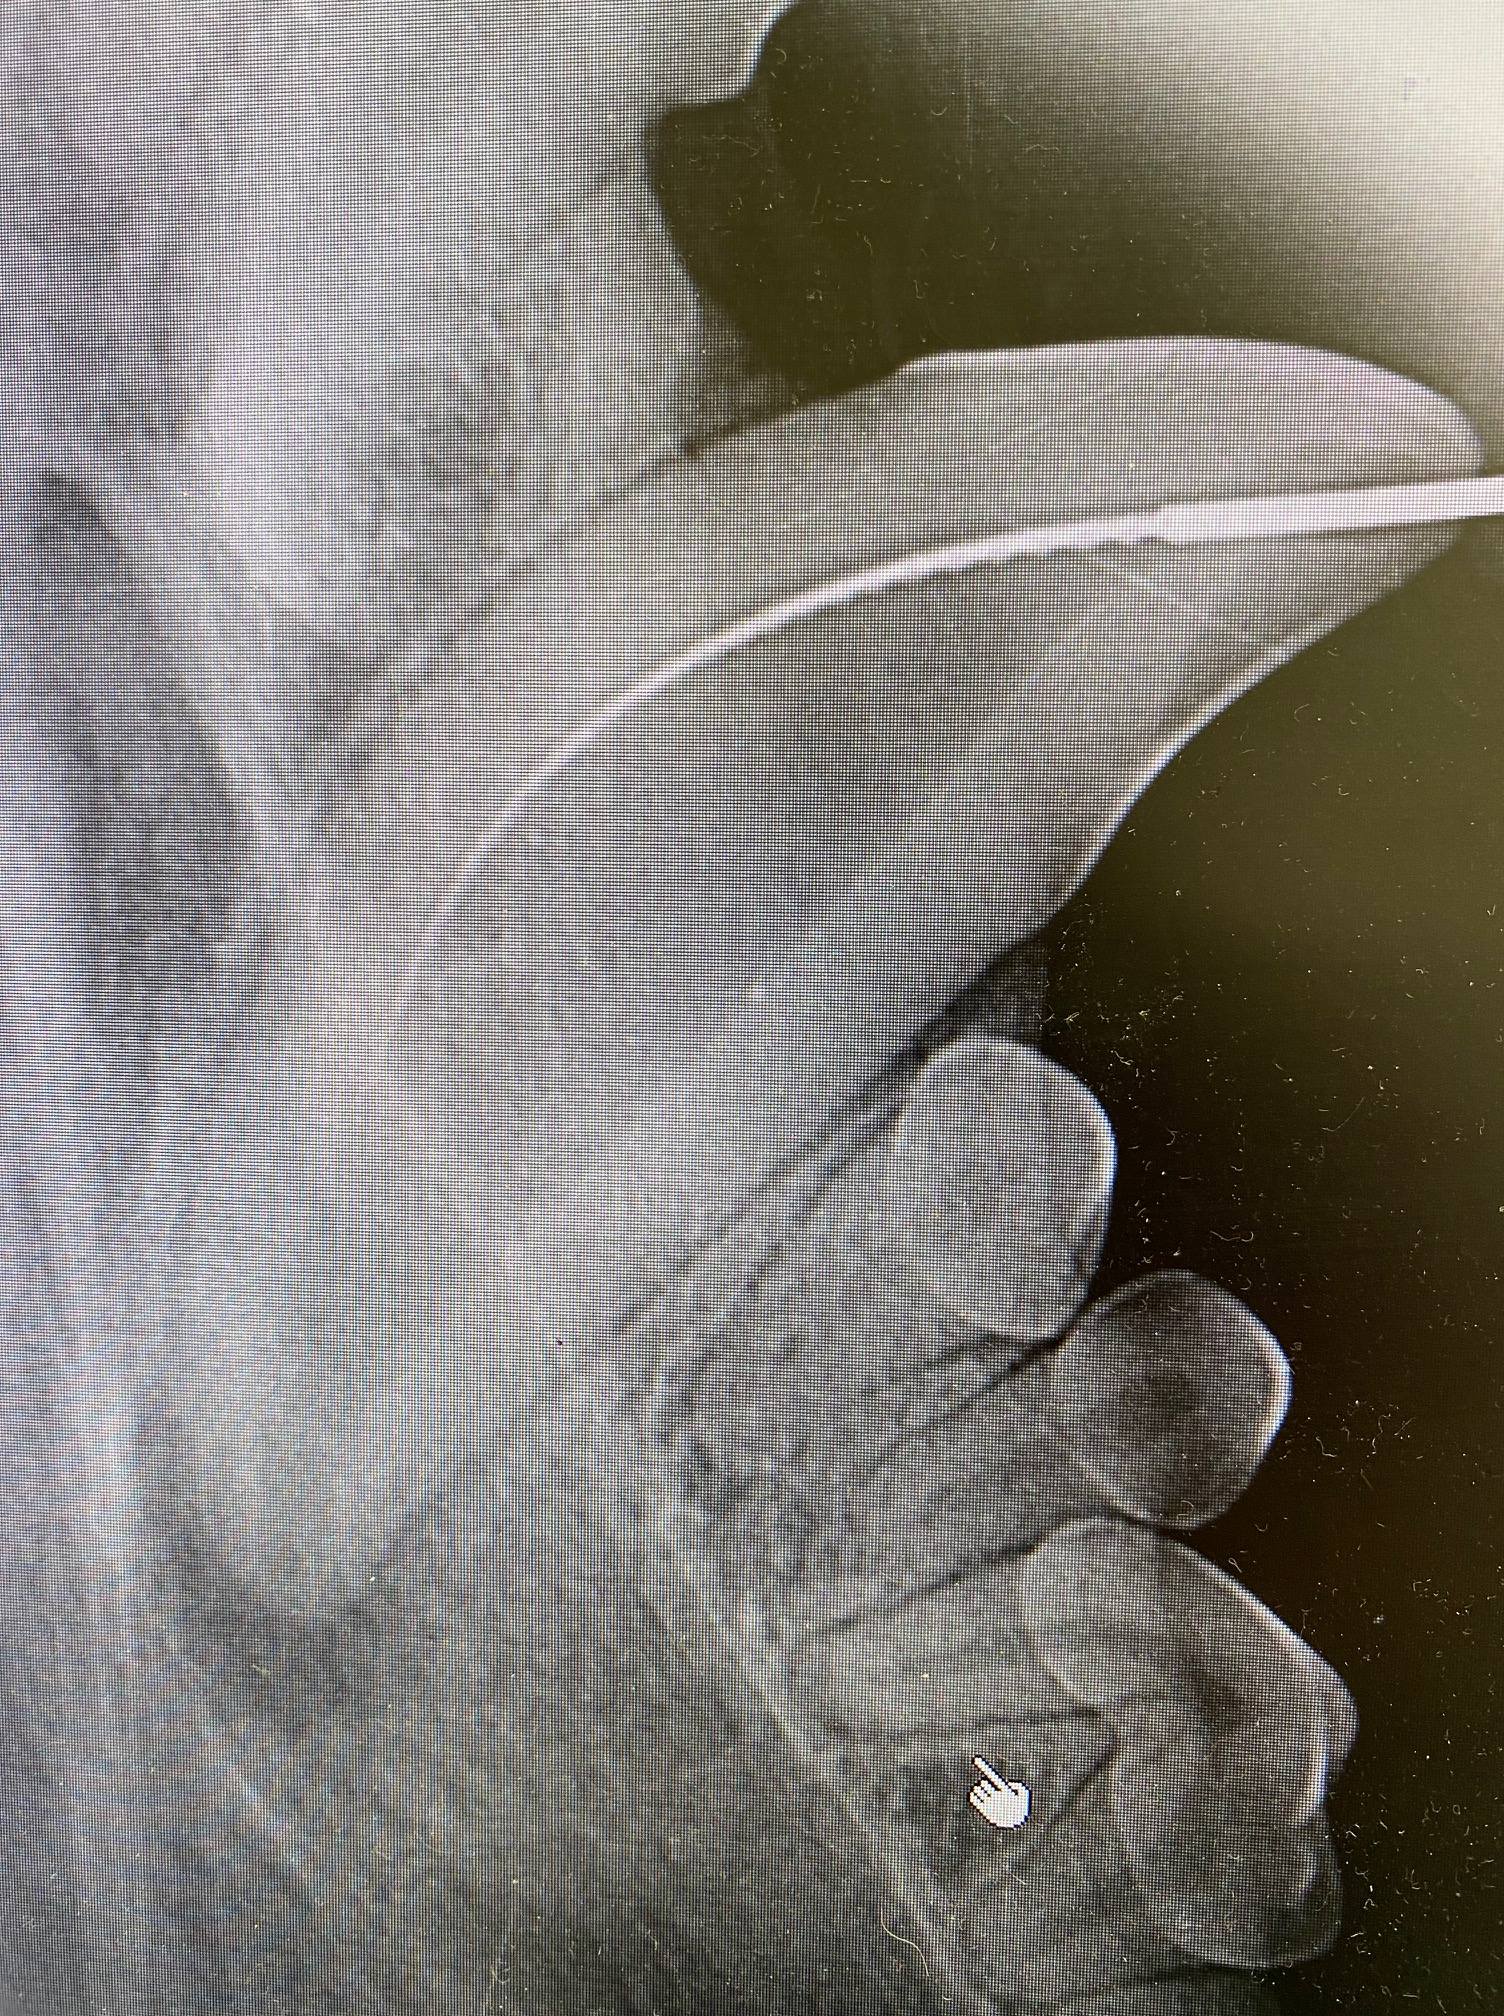

When under the anaesthetic the mouth could be properly examined, and a draining fistula identified at the point of the apex of the canine tooth, directly below 306. Pre op x-rays showed the the apex of the root of 304 was not closed. This means that most likely a traumatic incident occurred at the age of 9-12 months, causing the tooth to die and the normal development of the tooth to stop. As you can see in the x-ray, 304 has a much larger pulp than 404, indicating 304 is dead.

A root canal CAN NOT be done on this tooth as there is no “Stopper” at the apex of the pulp to contain the substances used to fill the tooth. (Note, however, that if the problem had been identified at the time, the tooth could have been filled with CaOH which can stimulate odontogenesis and the apex to close, meaning a root canal could be performed at a later date).

In this case, 304 had to be carefully extracted. This was done by making a gingival flap, burring away buccal and some lingual alveolar bone, and by using a vet tome, luxators, elevators and forceps. The photos show the open apex and thin dentine of 304 post extraction. A post op x-ray showed complete extraction of the root. The socket was curetted and flushed with copious amounts of saline. A periosteal releasing incision was made on the underside of the gingival flap and it was closed under no tension using 4/0 mono q absorbable suture material.